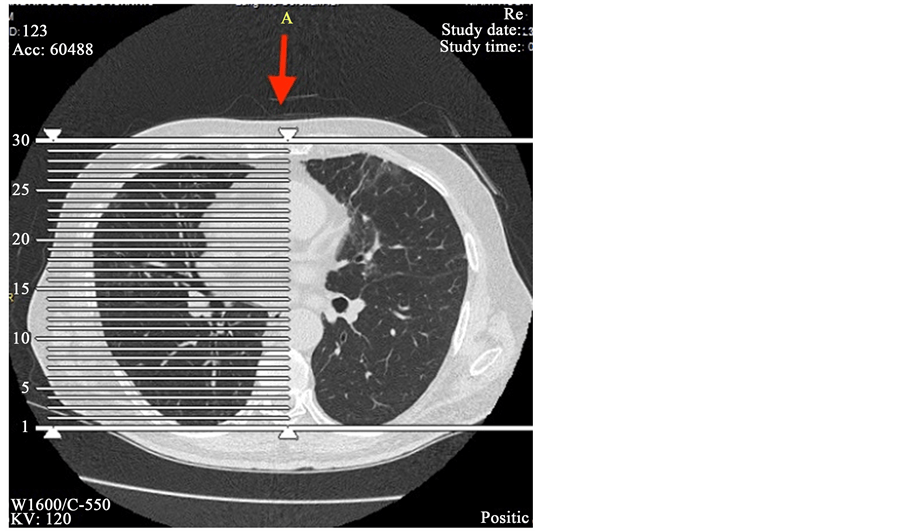

From www.researchgate.net

Chest Xray before discharge and after nitrofurantoin withdrawal Chest Pain After Taking Nitrofurantoin Headache* constipation* * to learn more about this side effect, see the “nitrofurantoin’s side effects explained” section. Symptoms of acute pulmonary reactions usually include fever, chills, cough, chest pain, dyspnoea, pulmonary infiltration with. The inflammation is usually accompanied by high. Difficulty breathing, fever, chills, chest pain and cough. You get pins and needles, tingling. Serious skin rash that looks red,. Chest Pain After Taking Nitrofurantoin.

From www.scirp.org

Pulmonary Fibrosis Due to Nitrofurantoin Therapy A Case Report Chest Pain After Taking Nitrofurantoin Symptoms of lung inflammation can include tiredness, fever, chills, cough, chest pain, and shortness of breath. Serious skin rash that looks red, swollen, blistered or peeling. Headache* constipation* * to learn more about this side effect, see the “nitrofurantoin’s side effects explained” section. Difficulty breathing, fever, chills, chest pain and cough. Symptoms of acute pulmonary reactions usually include fever, chills,. Chest Pain After Taking Nitrofurantoin.

Pulmonary Fibrosis Due to Nitrofurantoin Therapy A Case Report Chest Pain After Taking Nitrofurantoin Symptoms of acute pulmonary reactions usually include fever, chills, cough, chest pain, dyspnoea, pulmonary infiltration with. You get pins and needles, tingling. If you have any of these symptoms, contact your doctor right away. Headache* constipation* * to learn more about this side effect, see the “nitrofurantoin’s side effects explained” section. Difficulty breathing, fever, chills, chest pain and cough. Symptoms. Chest Pain After Taking Nitrofurantoin.

Chest Xray before discharge and after nitrofurantoin withdrawal Chest Pain After Taking Nitrofurantoin This rare possible side effect can occur after taking the medication for a very long time (over 6 months). Symptoms of lung inflammation can include tiredness, fever, chills, cough, chest pain, and shortness of breath. Difficulty breathing, fever, chills, chest pain and cough. Call 999 or go to a&e if: You get pins and needles, tingling. Headache* constipation* * to. Chest Pain After Taking Nitrofurantoin.